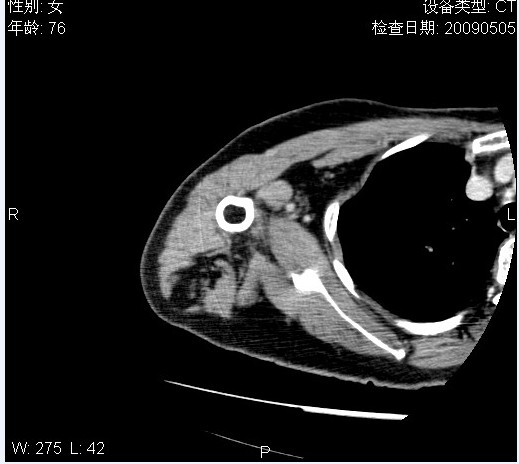

标题: CT19811:女,76岁,右上臂肿物1个月 [打印本页]

标题: CT19811:女,76岁,右上臂肿物1个月

使用了造影剂,可惜效果不太好

右肱骨上段软组织内见梭形低密度影,边界清楚,最长径约54mm.

病理结果:脂肪瘤。术中见肱骨骨膜受侵,有出血,量不详。

当时诊断意见:右肩三角肌内蔓状血管瘤(先天性动静脉瘘)。

本人对病理结果有个疑问:单纯的脂肪瘤内为什么有条状软组织影,那应该脂肪肉瘤才对啊?

该病例增强效果欠佳,由于经验欠缺,我们注射对比剂是由下肢足背静脉给药。注速2.0。虽然如此,但我们可以看到肿块内部条状软组织影是强化的,而且是连续的,并可见供血动脉是由腋动脉的其中一支即肩胛下动脉分出。从这些征象我们可以得出诊断:蔓状务血管瘤。

可病理偏偏为脂肪瘤,我怀疑取材有问题。因为蔓状血管瘤异常扩张的静脉外周是脂肪成分,它可以侵犯肌组织及骨骼。当取材于外周,那当然是脂肪瘤。此时我认为临床的最终诊断不应单从病理出发,应该综合考虑。